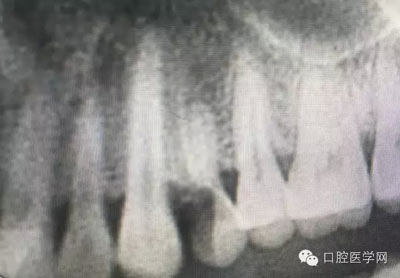

根管治療,我們在大學的時候就學習的東西,標準就在那里放著,可是很多時候我們熟視無睹,放任我們的想象去做。我們多些重視,多些心思,會好很多,認真對待每顆牙齒。